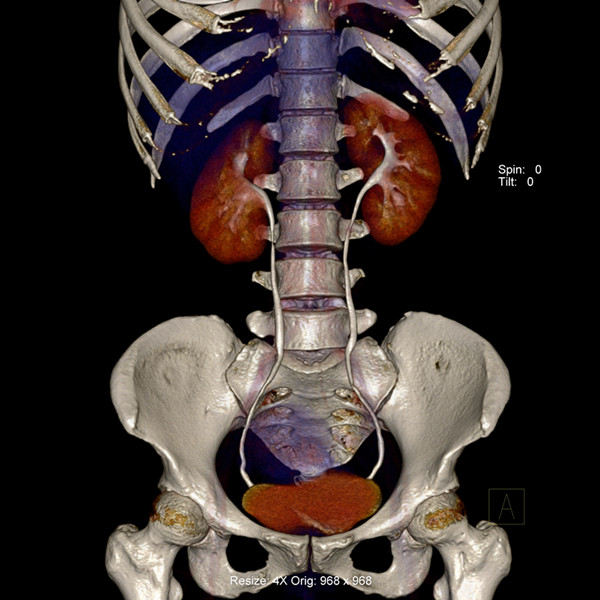

炫速雙源CT是目前世界上最先進的CT設(shè)備之一。它采用兩套64排圖像采集系統(tǒng),結(jié)合“飛焦點”技術(shù),并且有超高的旋轉(zhuǎn)速度,能夠在極短的時間內(nèi)完成掃描,為病人提供“綠色” CT 檢查。它的特點是炫速掃描技術(shù) (Flash Spiral),即大螺距的螺旋掃描,可以在一秒鐘之內(nèi)完成掃描,同時輻射劑量極低。 它的主要特色掃描技術(shù)如下:

純譜雙能 選擇性能譜純化技術(shù)(SPS)實現(xiàn)常規(guī)輻射劑量下的雙能量成像。憑借能譜純化技術(shù)以及獲得美國 FDA 上市許可的多項雙能量臨床應(yīng)用,第二代雙能量成像 將成為日常臨床應(yīng)用的完美選擇。

輻射敏感器官的射線保護 可自動屏蔽螺旋掃描中的無效輻射,并首次針對輻射敏感器官實現(xiàn)特異性輻射防護技術(shù)。  炫速雙源CT的適應(yīng)癥很廣泛,對心血管系統(tǒng)疾病的診斷幫助較大,是冠狀動脈疾病檢查的利器。適合于:

6、冠狀動脈解剖學(xué)異常,為先天性疾病,雖然少見,但是突發(fā)的心肌梗死和猝死的重要病因,是年輕的運動員猝死的第二位病因,通過炫速雙源CT檢查,可發(fā)現(xiàn)是冠狀動脈的起源異常、走行異?;蚴墙K止位置異常,發(fā)現(xiàn)后可及早進行有效的治療,盡量避免猝死的發(fā)生。

7、病人因胸痛急診時,快速獲得準(zhǔn)確的診斷是關(guān)鍵。對于具有極高時間分辨率的炫速雙源CT來說,不但可以輕松完成常規(guī)檢查,而且可以對特別嚴(yán)重的急診患者完成“一站式”診斷,對急性胸痛患者通過一次注射對比劑同時獲得冠脈CTA、肺動脈CTA及主動脈CTA,可明確胸痛病因是心臟冠脈疾病、肺動脈栓塞還是主動脈夾層,具有非常實用的臨床價值。